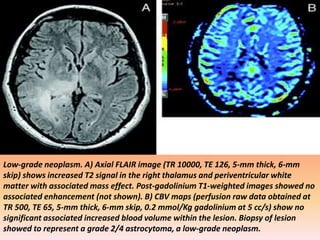

Low-grade neoplasm. A) Axial FLAIR image (TR 10000, TE 126, 5-mm thick, 6-mm

skip) shows increased T2 signal in the right thalamus and periventricular white

matter with associated mass effect. Post-gadolinium T1-weighted images showed no

associated enhancement (not shown). B) CBV maps (perfusion raw data obtained at

TR 500, TE 65, 5-mm thick, 6-mm skip, 0.2 mmol/Kg gadolinium at 5 cc/s) show no

significant associated increased blood volume within the lesion. Biopsy of lesion

showed to represent a grade 2/4 astrocytoma, a low-grade neoplasm.